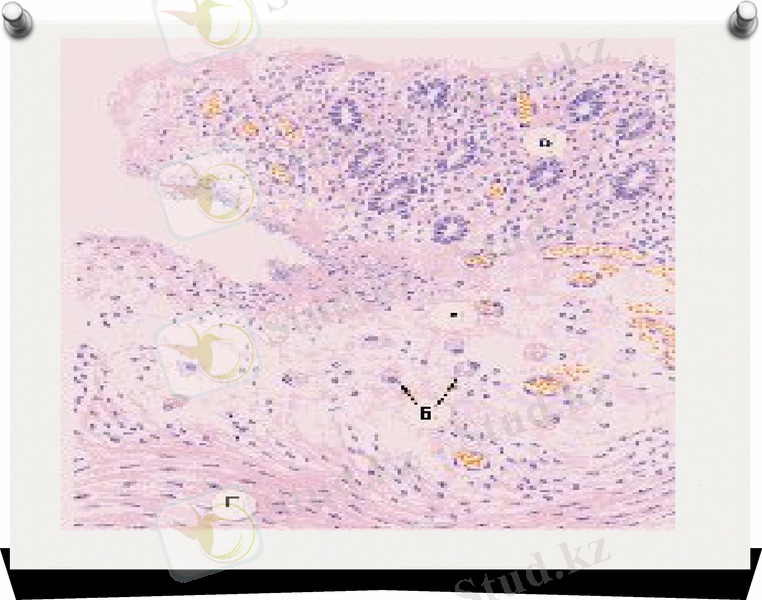

K. ozaenae танаудың шырышты қабатын және оның қосалқы кеңістігінде, атрофиясын шақырада, қабыну барысында жағымсыз иісті бөлінді бөлінеді. K. rinoscleromatis мұрынның шырышты қабатын ғана. емес, трахеяны, бронхты, жұтқыншақты, аңқаны жарақаттайды, осы жағдайда жарақатталған ұлпада, шеміршек тәрізді инфильтратқа алып келетін арнайы гранулема пайда болады. Ауру созылмалы түрде жүреді, трахеяны, аңқаның кепгелінің (обтурациясының) нәтижесі өлімге алып келеді.